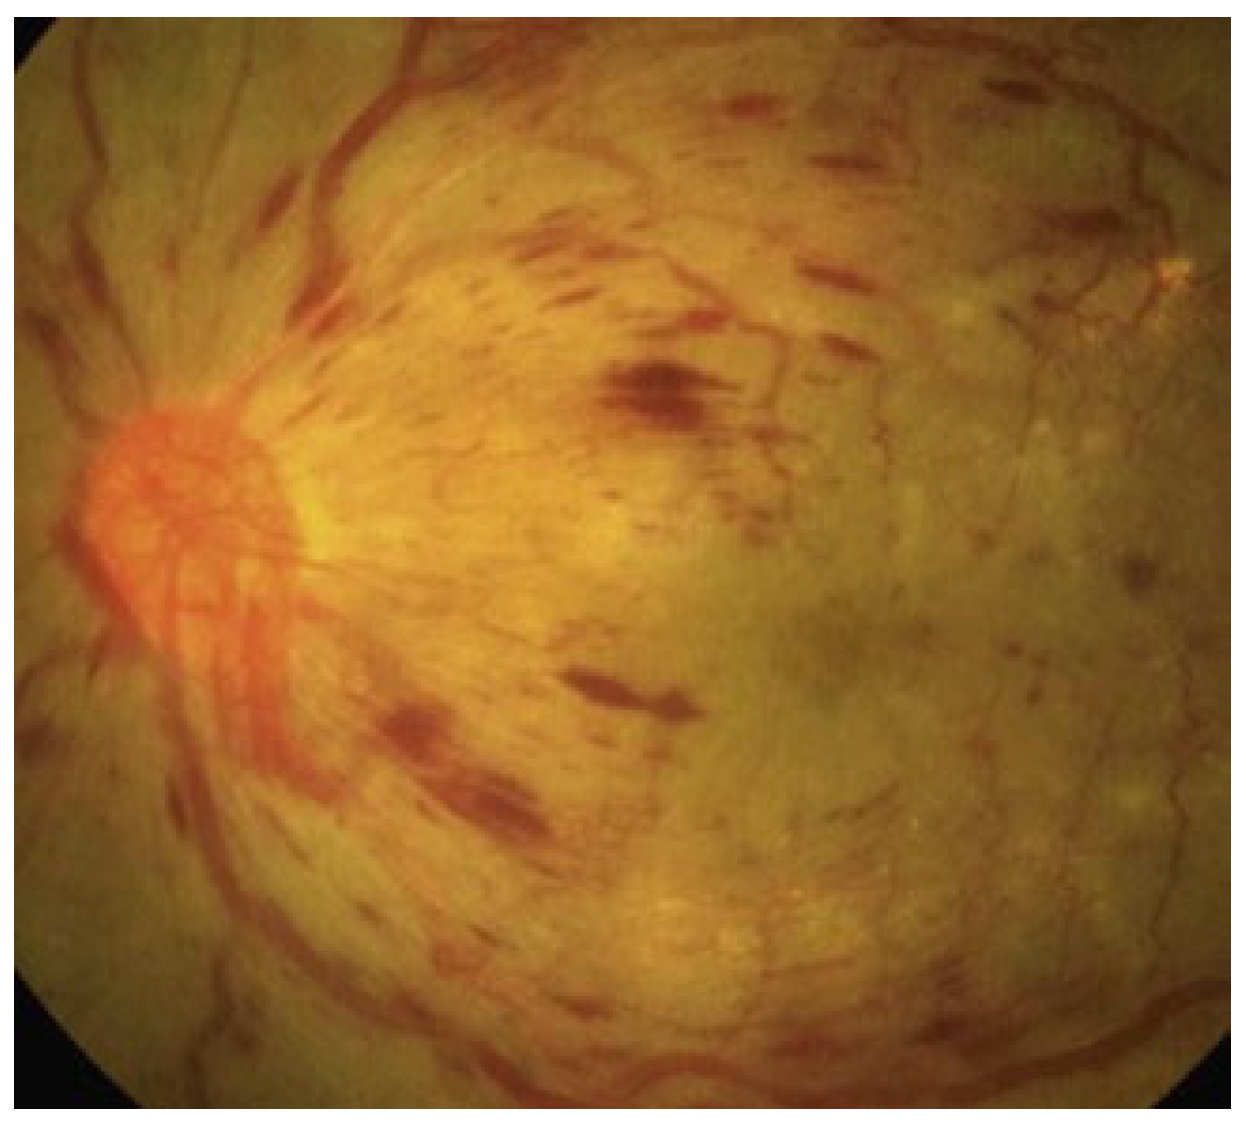

2. Diabetic Retinopathy: Clinical Features and Stages

2.1. Non-Proliferative Diabetic Retinopathy (NPDR) and Proliferative Diabetic Retinopathy (PDR)